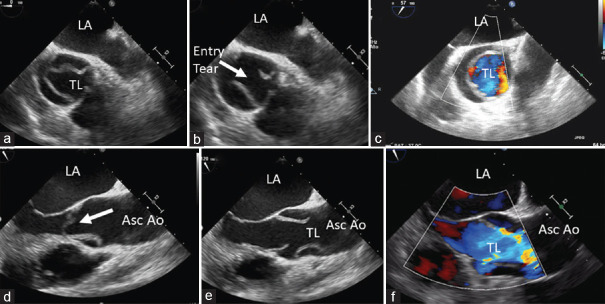

Acute aortic syndromes comprise a range of interrelated conditions including aortic dissection, intramural hematoma, penetrating atherosclerotic ulcer, and contained or not contained aortic aneurysm rupture. These syndromes are potentially life threatening; therefore, a rapid and accurate diagnosis is crucial. A new Clinical Consensus Statement on Aortic and Peripheral Vascular Disease has recently been published, and we will try to highlight the main innovations in the document.